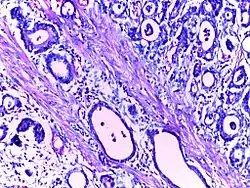

Adenocarcinoma stomach | Micrograph of carcinoma stomach. The glands are seen infiltrating the muscle layer. The neoplastic cells are arranged in cords and in glandular pattern. The cells show dysplastic features. Signet rings with nucleus pushed to the periphery are seen in some types of adenocarcinoma. | Category: Histopathology of adenocarcinoma stomach | Adenocarcinoma of stomach |

![]() |